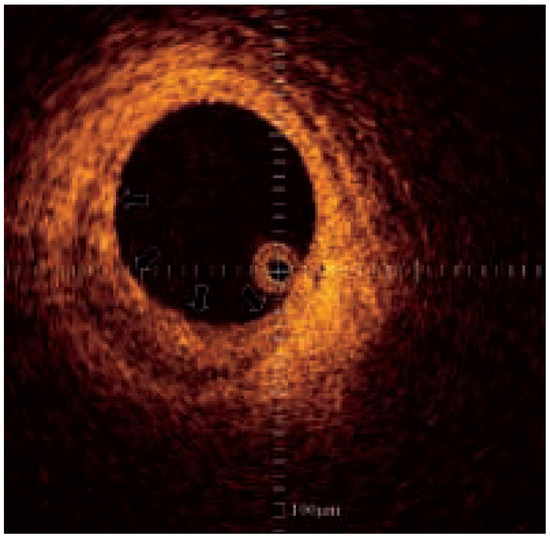

Diabetes leads to both micro- and macrovascular complications. If the major threat to type 2 diabetic patients is ischaemic heart disease, other cardiovascular complications such as heart failure, stroke and lower extremity arterial disease are also...